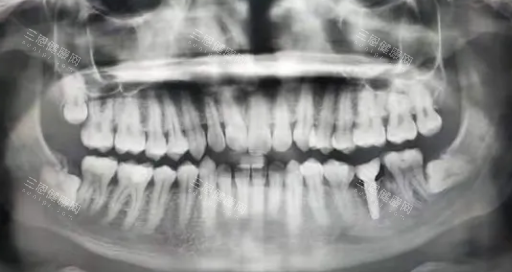

“28岁程序员小李捂着半边脸冲进诊室,嘴里直抽冷气:‘医生,我这智齿疼了三天三夜,连代码都写不利索了!’可拍完片才发现,他疼的压根不是智齿,而是颗‘潜伏’多年的阻生齿!”这样的乌龙事件,在口腔科每天都在上演。智齿和阻生齿,这对让无数人闻之色变的“牙齿刺客”,到底藏着多少秘密?今天咱们就掰开揉碎,用4大核心差异,揭开它们的真面目!

但阻生齿的“黑历史”更复杂!它可以是任何一颗牙——前磨牙、尖牙甚至多生牙,只要因为空间不足、位置歪斜、牙龈覆盖等原因“卡壳”长不出来,都能被扣上“阻生齿”的帽子。就像北京胡同里停错车位的汽车,不管你是奔驰还是五菱,只要堵了路,都得被贴条!

“智齿是‘麻烦制造者’,阻生齿却是‘定时炸弹’!”这句话虽然夸张,却道出了两者的危害差异。智齿的“作妖”方式比较单一:要么因为空间不足,把邻牙“挤”歪;要么因为清洁困难,引发智齿冠周炎(表现为牙龈肿痛、张口受限);少数情况下,水平阻生的智齿还可能压迫下颌神经,导致嘴唇麻木。

阻生齿的破坏力则堪称“多面手”!它可能是“邻牙杀手”——与第二磨牙之间形成“卫生死角”,引发龋齿、牙髓炎;可能是“颌骨破坏者”——长期刺激周围组织,形成含牙囊肿甚至颌骨骨髓炎;还可能是“美貌杀手”——导致牙列拥挤、咬合紊乱,让脸型变丑。更可怕的是,阻生齿引发的感染可能扩散至全身,引发脓毒血症等致命并发症!